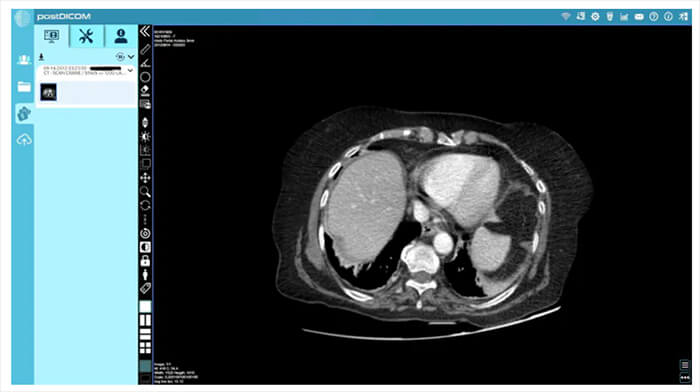

Post DICOM image

To view these images on your computer, you will have to use a DICOM viewer, which will interpret the file information and display it as an image. There are many different viewers available. One such viewer, Post DICOM, is an online radiology/ DICOM-sharing service. It provides a cloud with 50GB of free space for uploading, organizing and sharing DICOM files, and it comes with a powerful DICOM viewer. It allows you to organize your files as well as search cases by patient name, patient ID or case number.